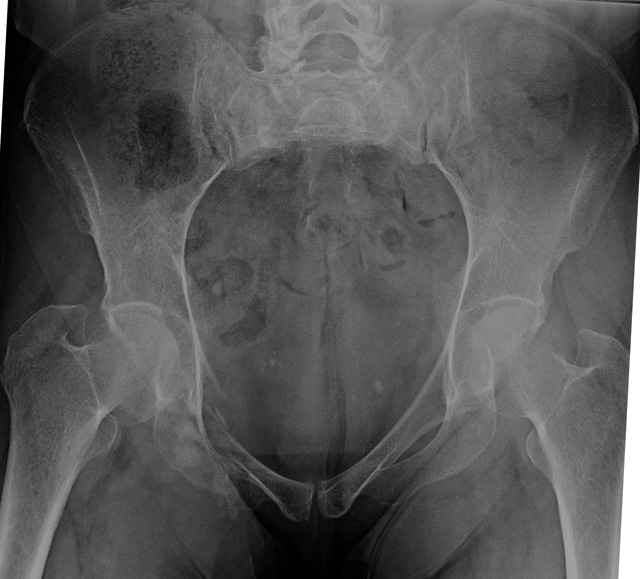

54 yo Female Fell c/o Pain

Initial Films

?Instability on Exam - Limited by Pain

NonOp Initial Mgmt